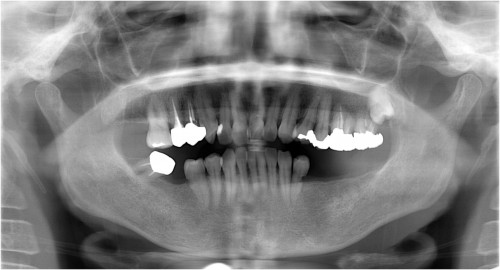

術前

下両奥歯 被せ物装着後